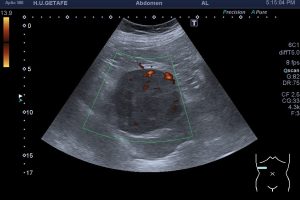

Un tumor renal suele comportarse de otro modo, siendo heterogéneo, con vascularización caótica y rechazando vasos, como tienes en la imagen 6 justo debajo de este texto.